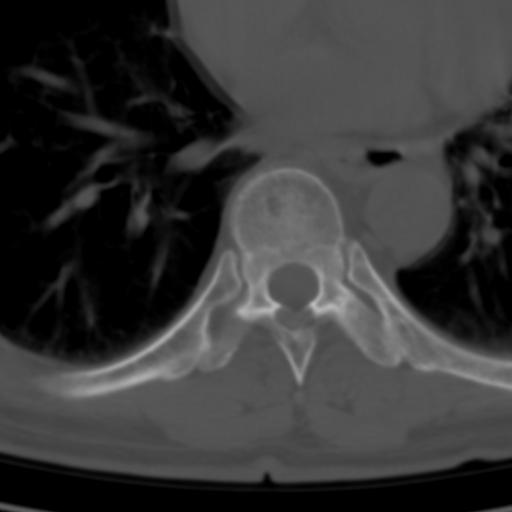

标题: CT25189:胸椎ct,请会诊!

既往食管癌,现行ct检查!

中上段食道癌,椎体轻度退变。

支持中上段食道癌,椎体轻度退变,必要时做ect。